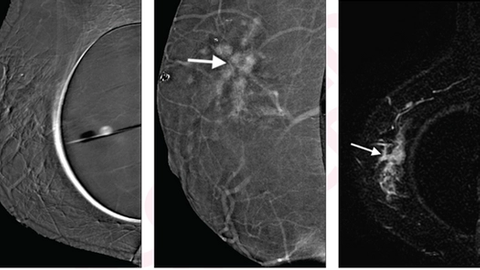

40-Year-Old Woman with Invasive Ductal Carcinoma of Right Breast

According to their analysis, CEM and MRI results were consistent for all 17 women. Specifically, the team identified invasive ductal carcinoma in 15 women (88 percent), as well as invasive lobular carcinoma and ductal carcinoma in situ in one woman (6 percent) each. The average size of all tumors was 2 cm with two being mammographically occult, highlighting the decreased sensitivity of mammography in asymptomatic women with breast augmentation.

In addition, six other CEM-detected lesions found in six women (35 percent) were confirmed by MRI – three were multi-focal, two were contralateral, and one was multi-centric. Further analysis revealed two were malignant – one invasive ductal carcinoma and one invasive lobular carcinoma. The team noted that MRI did not pick up any cancers not seen on CEM.